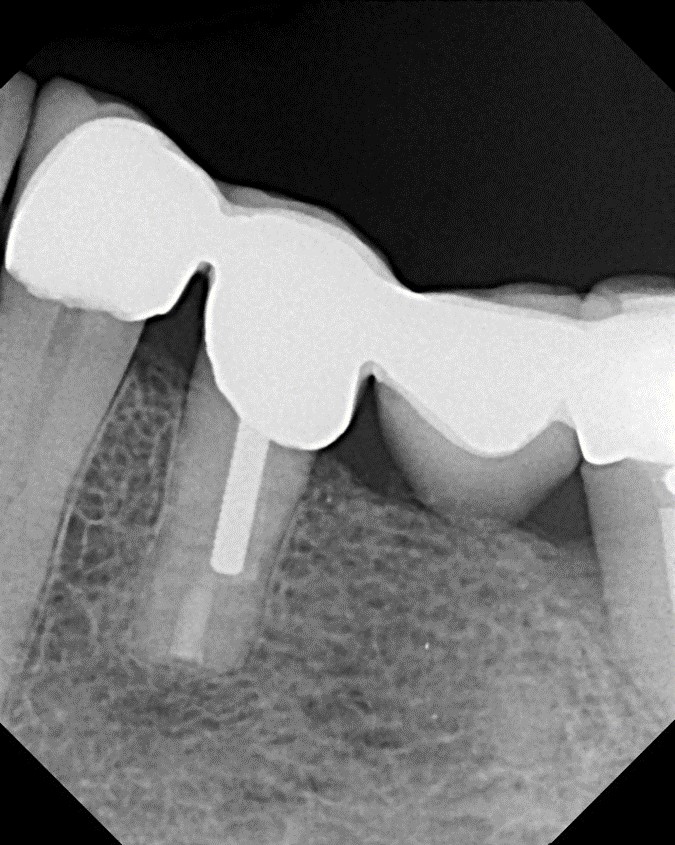

With this technology, gentle vortical flow is induced within the root canal system with a slight negative pressure at the apices, which reduces the potential for extrusion. The result is a more complete removal of pulp tissue, bacteria, and bacterial biofilm within the root canal, including debris in anatomically complex structures (eg, isthmi, lateral canals, multiple apical foramina).18-20 In other words, it can clean and disinfect even where a file or rotary instrument cannot reach (Figure 15 through Figure 18). All this is accomplished with minimal instrumentation, most of the time to a size as small as a .04 taper #15 or #20 rotary instrument. In addition, conservation of root dentin results in a stronger root, which may increase the survival rate of the treated tooth.7

Fig 16. Postoperative obturation radiographs after multisonic ultracleaning technology, revealing complex and intricate canal anatomy.

Figure 16